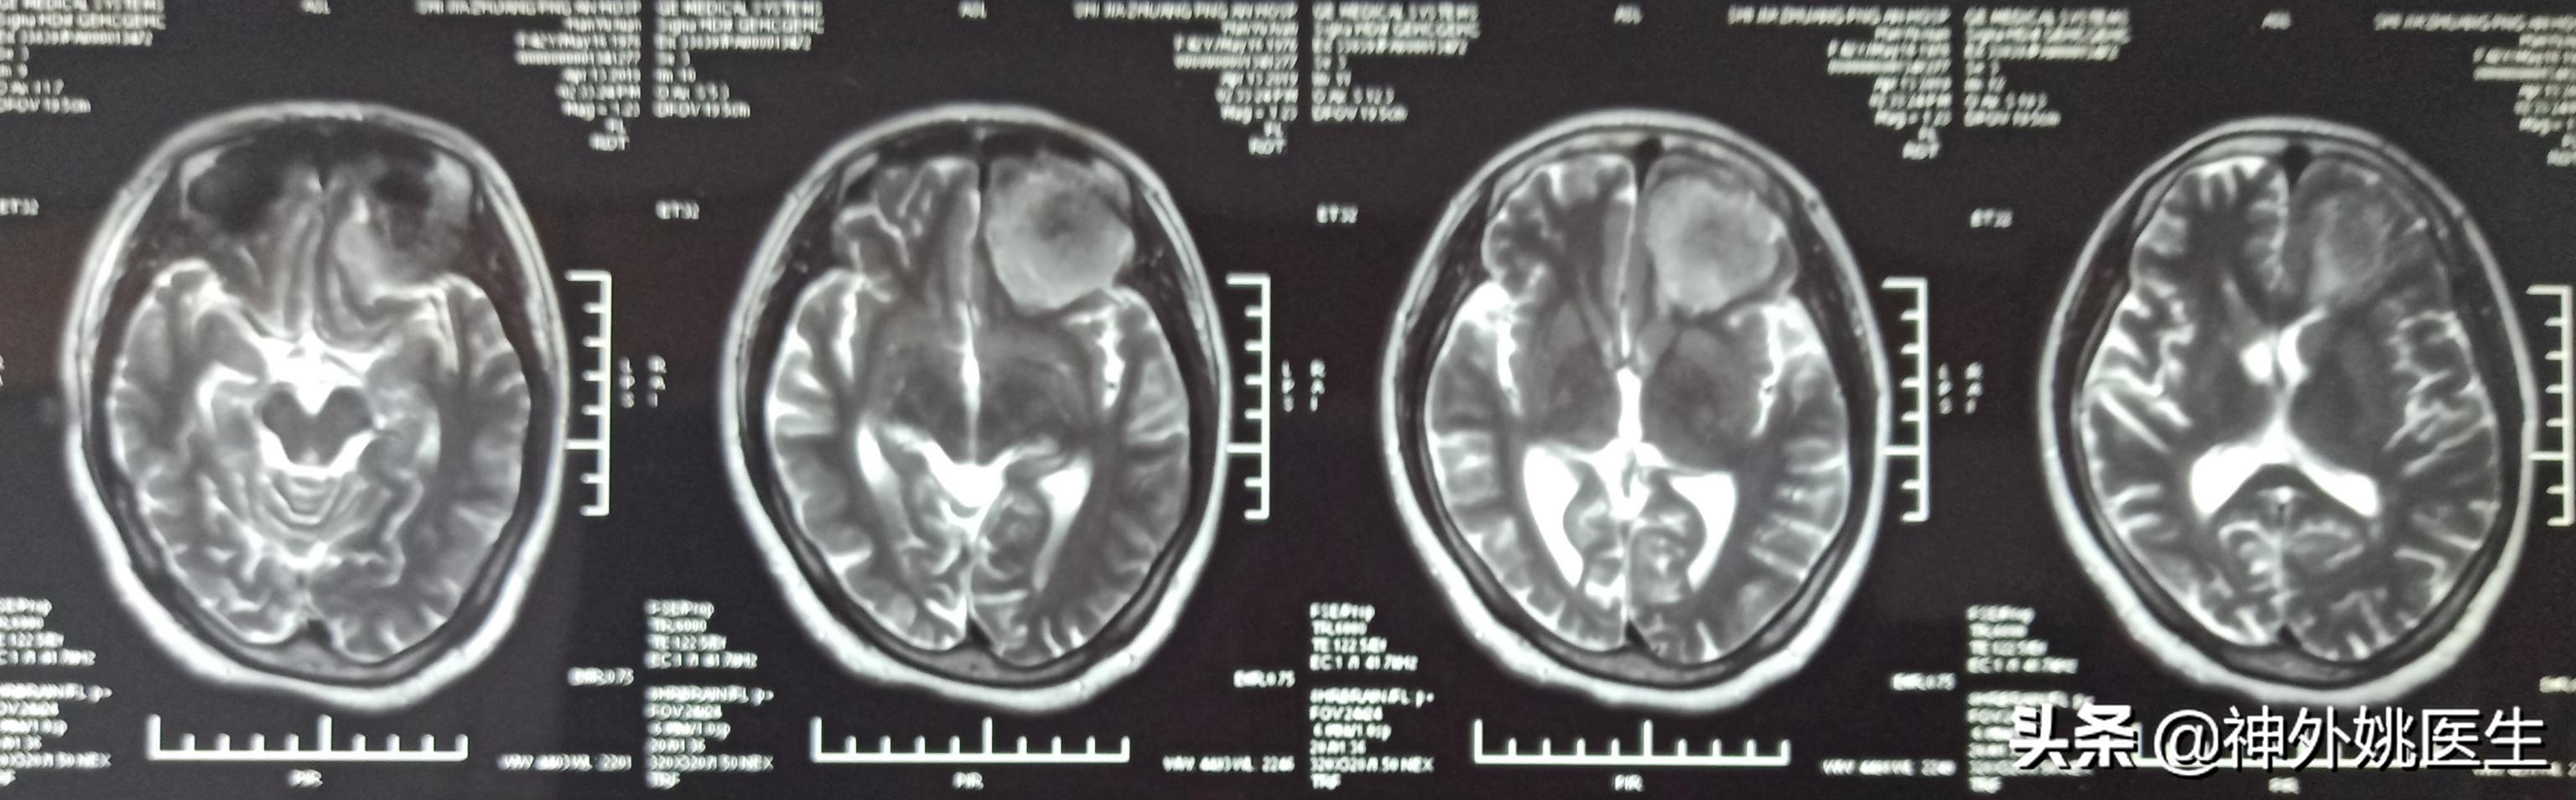

头MRI检查:1、左额部脑膜瘤。2、左侧放射冠区腔隙性脑梗死。(图3-7)

图4 T1像病变呈稍长T2信号。

图5 T2Flair像病变呈稍高T2信号。

图7 病变基底位于颅底硬膜,可见脑膜尾征,病变大小约3.8cm x 4.1cm x 2.9cm。